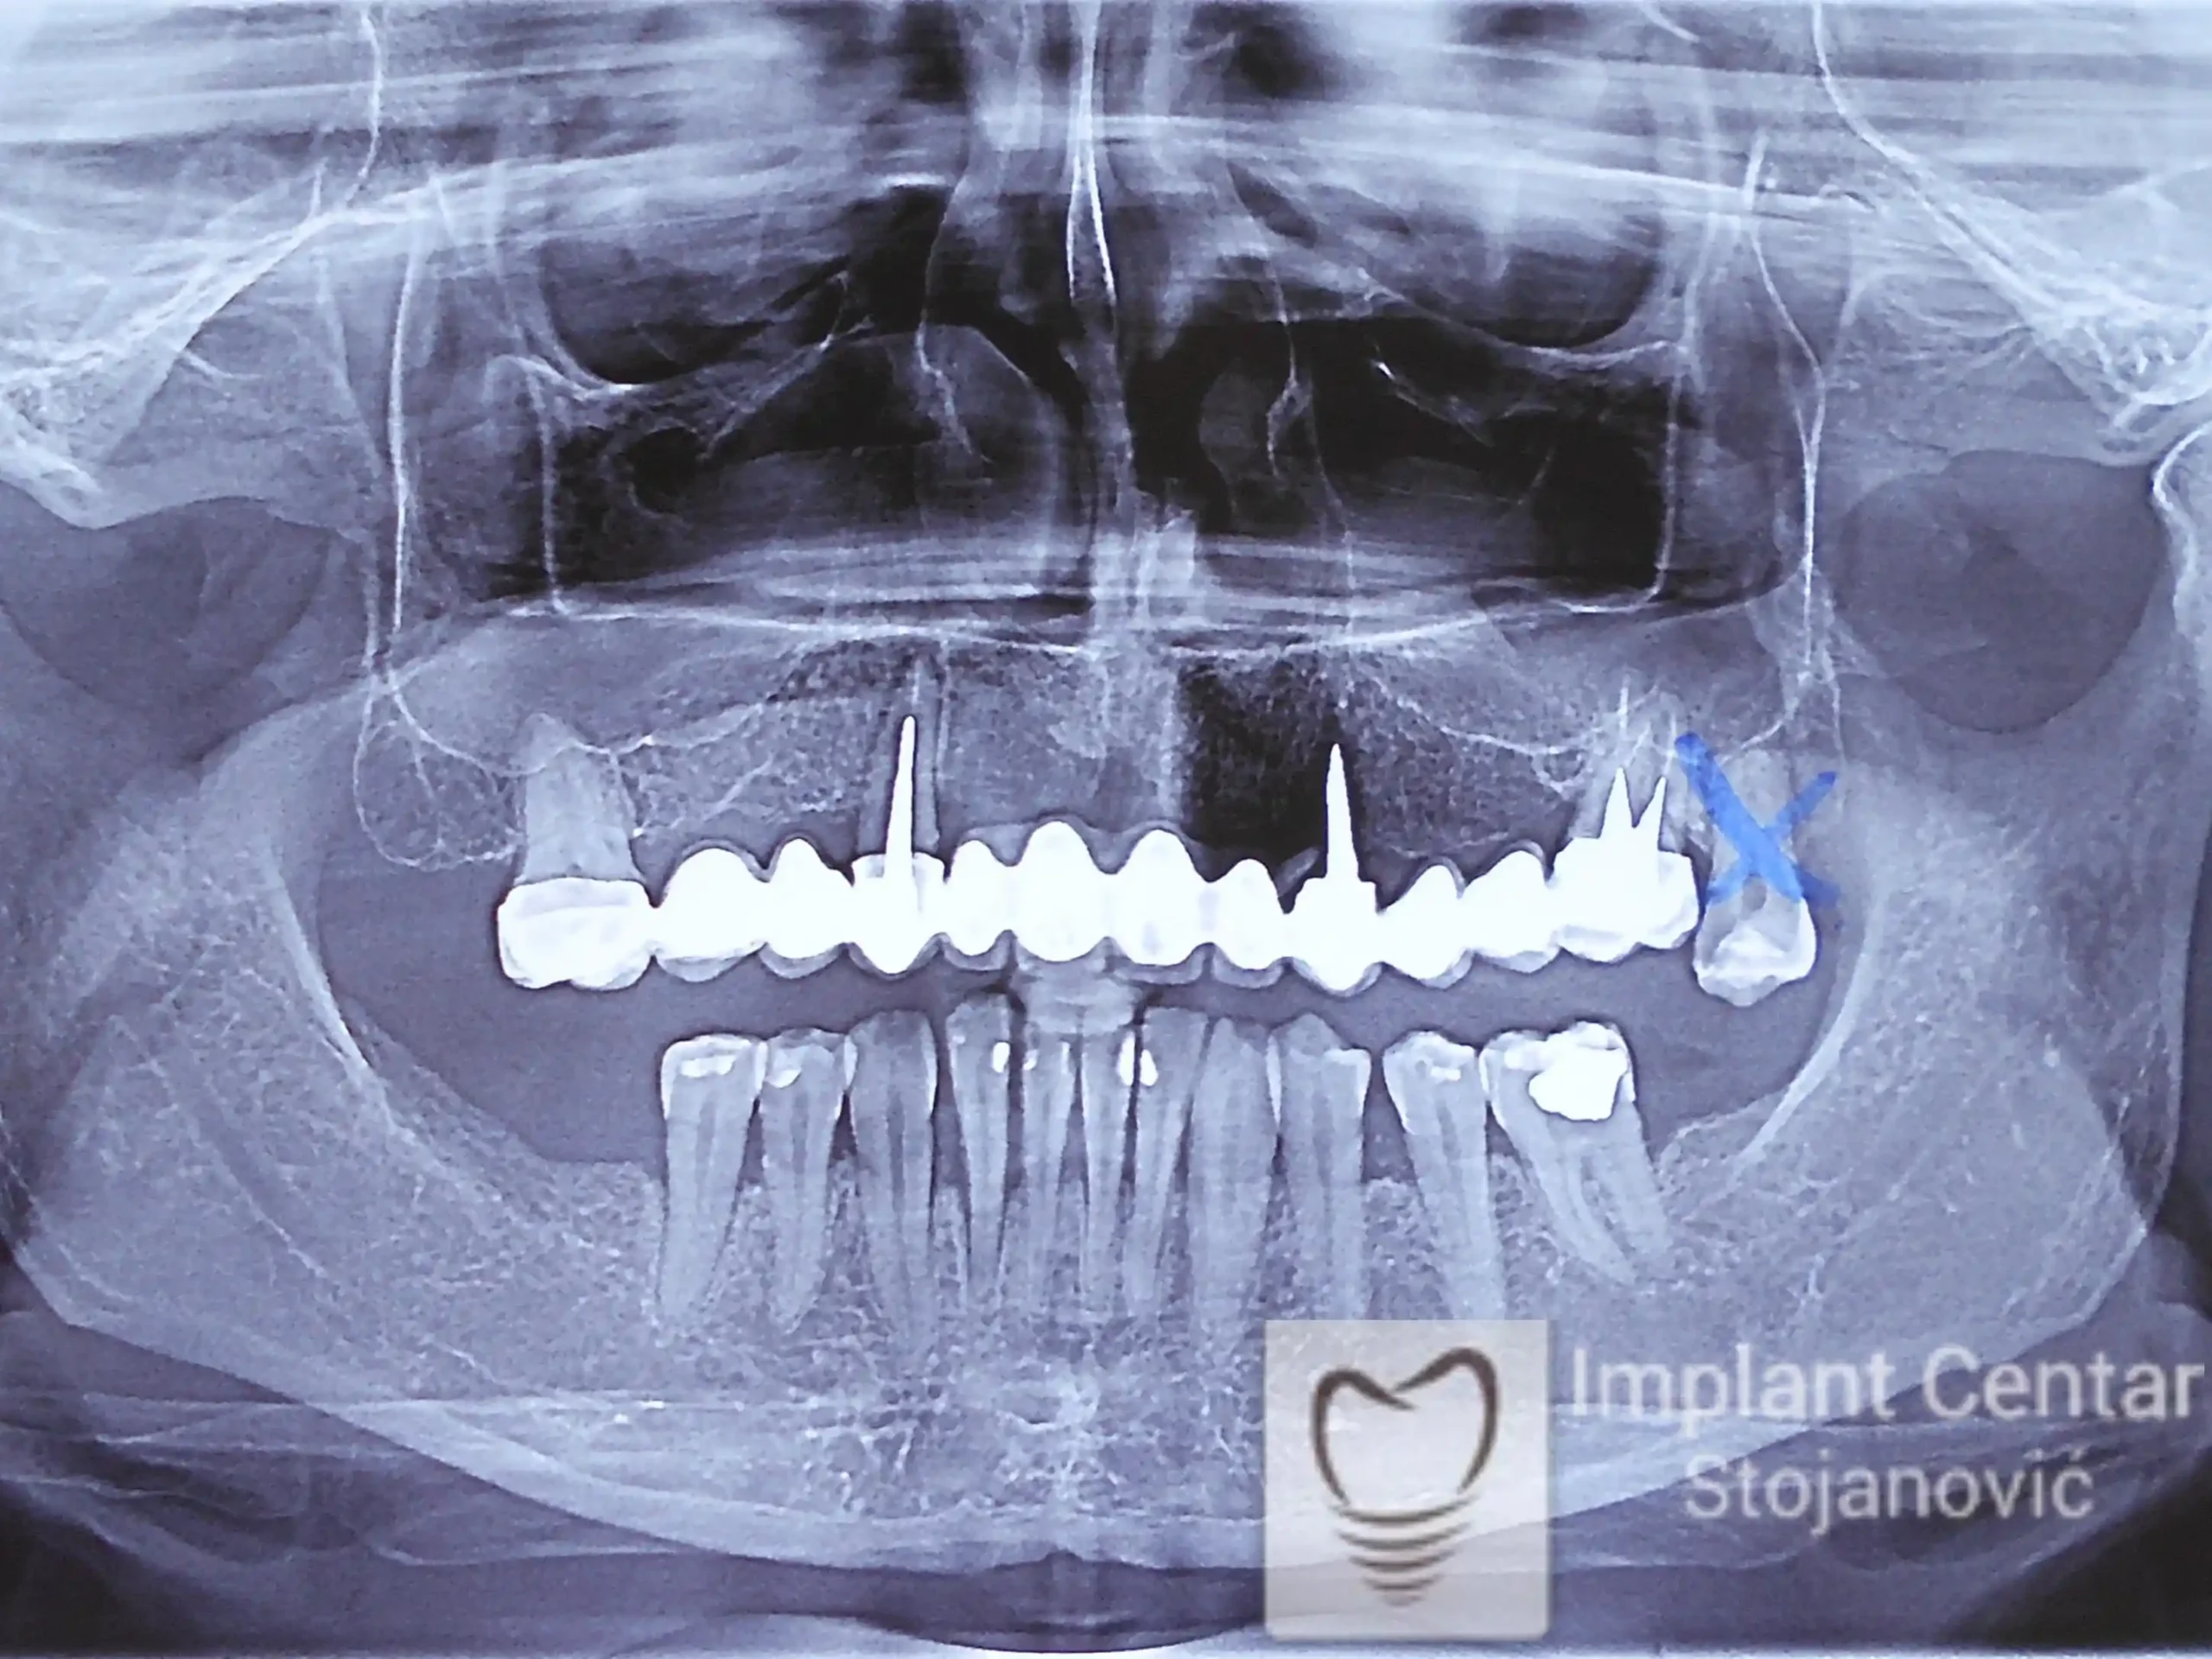

Na slici 1. i slici 2. prikazan je izgled pacijenta pre početka terapije – klinički i rendgenološki.

Nakon vađenja zuba, ugrađeni su implantati. Na slici 3 prikazan je ortopan snimak sa ugrđenim implantatima. Tokom perioda osteointegracije, pacijent je bio zbrinut fiksnim privremenim krunicama na implantatima, koje su izrađene samo dva dana nakon hirurške intervencije.